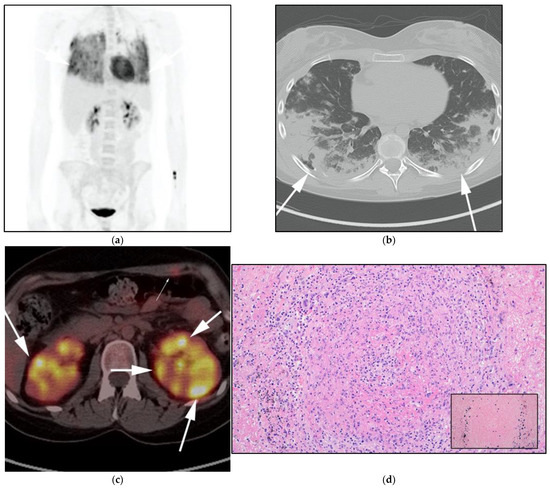

Figure 4.

A 30-year-old male with known history of autoimmune lymphoproliferative disorder since childhood. (a) Maximal intensity projection (MIP) FDG PET/CT image shows generalized hypermetabolic lymphadenopathy throughout the head, neck, chest, abdomen, and pelvis (white arrows). Note that splenic activity is not visualized (thin white arrow) because the spleen was surgically removed during childhood due to splenomegaly. (b) Axial FDG PET image shows hypermetabolic adenopathy within pelvis mainly about the bilateral pelvic side wall and external iliac nodes (white arrows). Lymph nodes often show little or only modest uptake, a clue, in addition to stability of nodal size and over multiple time points. Biopsy is the only method for definitive diagnosis. (c) H&E section of a lymph node shows highly proliferative paracortical expansion composed of small proliferative lymphocytes and immunoblasts with preserved lymphoid follicular architecture. There is sinus histiocytosis. (Original magnification 400×, H&E stain).

Once the diagnosis of ALPS is established, baseline and periodic follow-up CT scans should therefore be obtained to document the stability of lymphadenopathy and hepatosplenomegaly. 18F-FDG PET/CT may also be helpful because mild to moderate FDG uptake is typical of ALPS compared to the high FDG uptake characteristic of malignant lymphomas. By evaluating for areas of high FDG uptake, 18F-FDG PET/CT may help in the early detection of lymphoma transformation and demonstrate the best site for biopsy, when indicated [23]. Awareness of ALPS is pivotal because ALPS often requires long-term immunosuppressive therapies as opposed to chemotherapy that is standard for malignant lymphoproliferative disorders.

Imaging is not necessary to establish a diagnosis of ALPS but might aid in its diagnostic evaluation. Stability in the size of lymphadenopathy and hepatosplenomegaly over many years may suggest ALPS from other malignant lymphoproliferative diseases [26] (Figure 4).